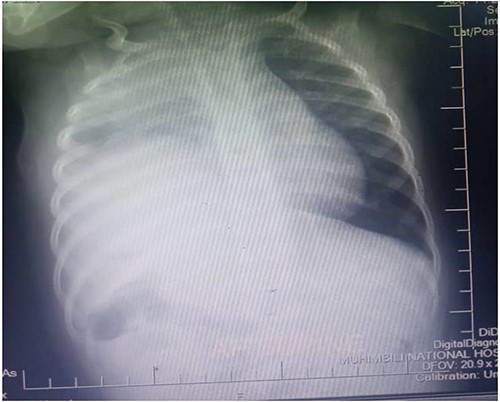

Figure 4 shows a control plain chest radiography taken after the right hemidiaphragmatic repair, it describing adequate right lung volume of expansion, with normal hemidiaphragmatic dome and obvious cardiac silhouette.